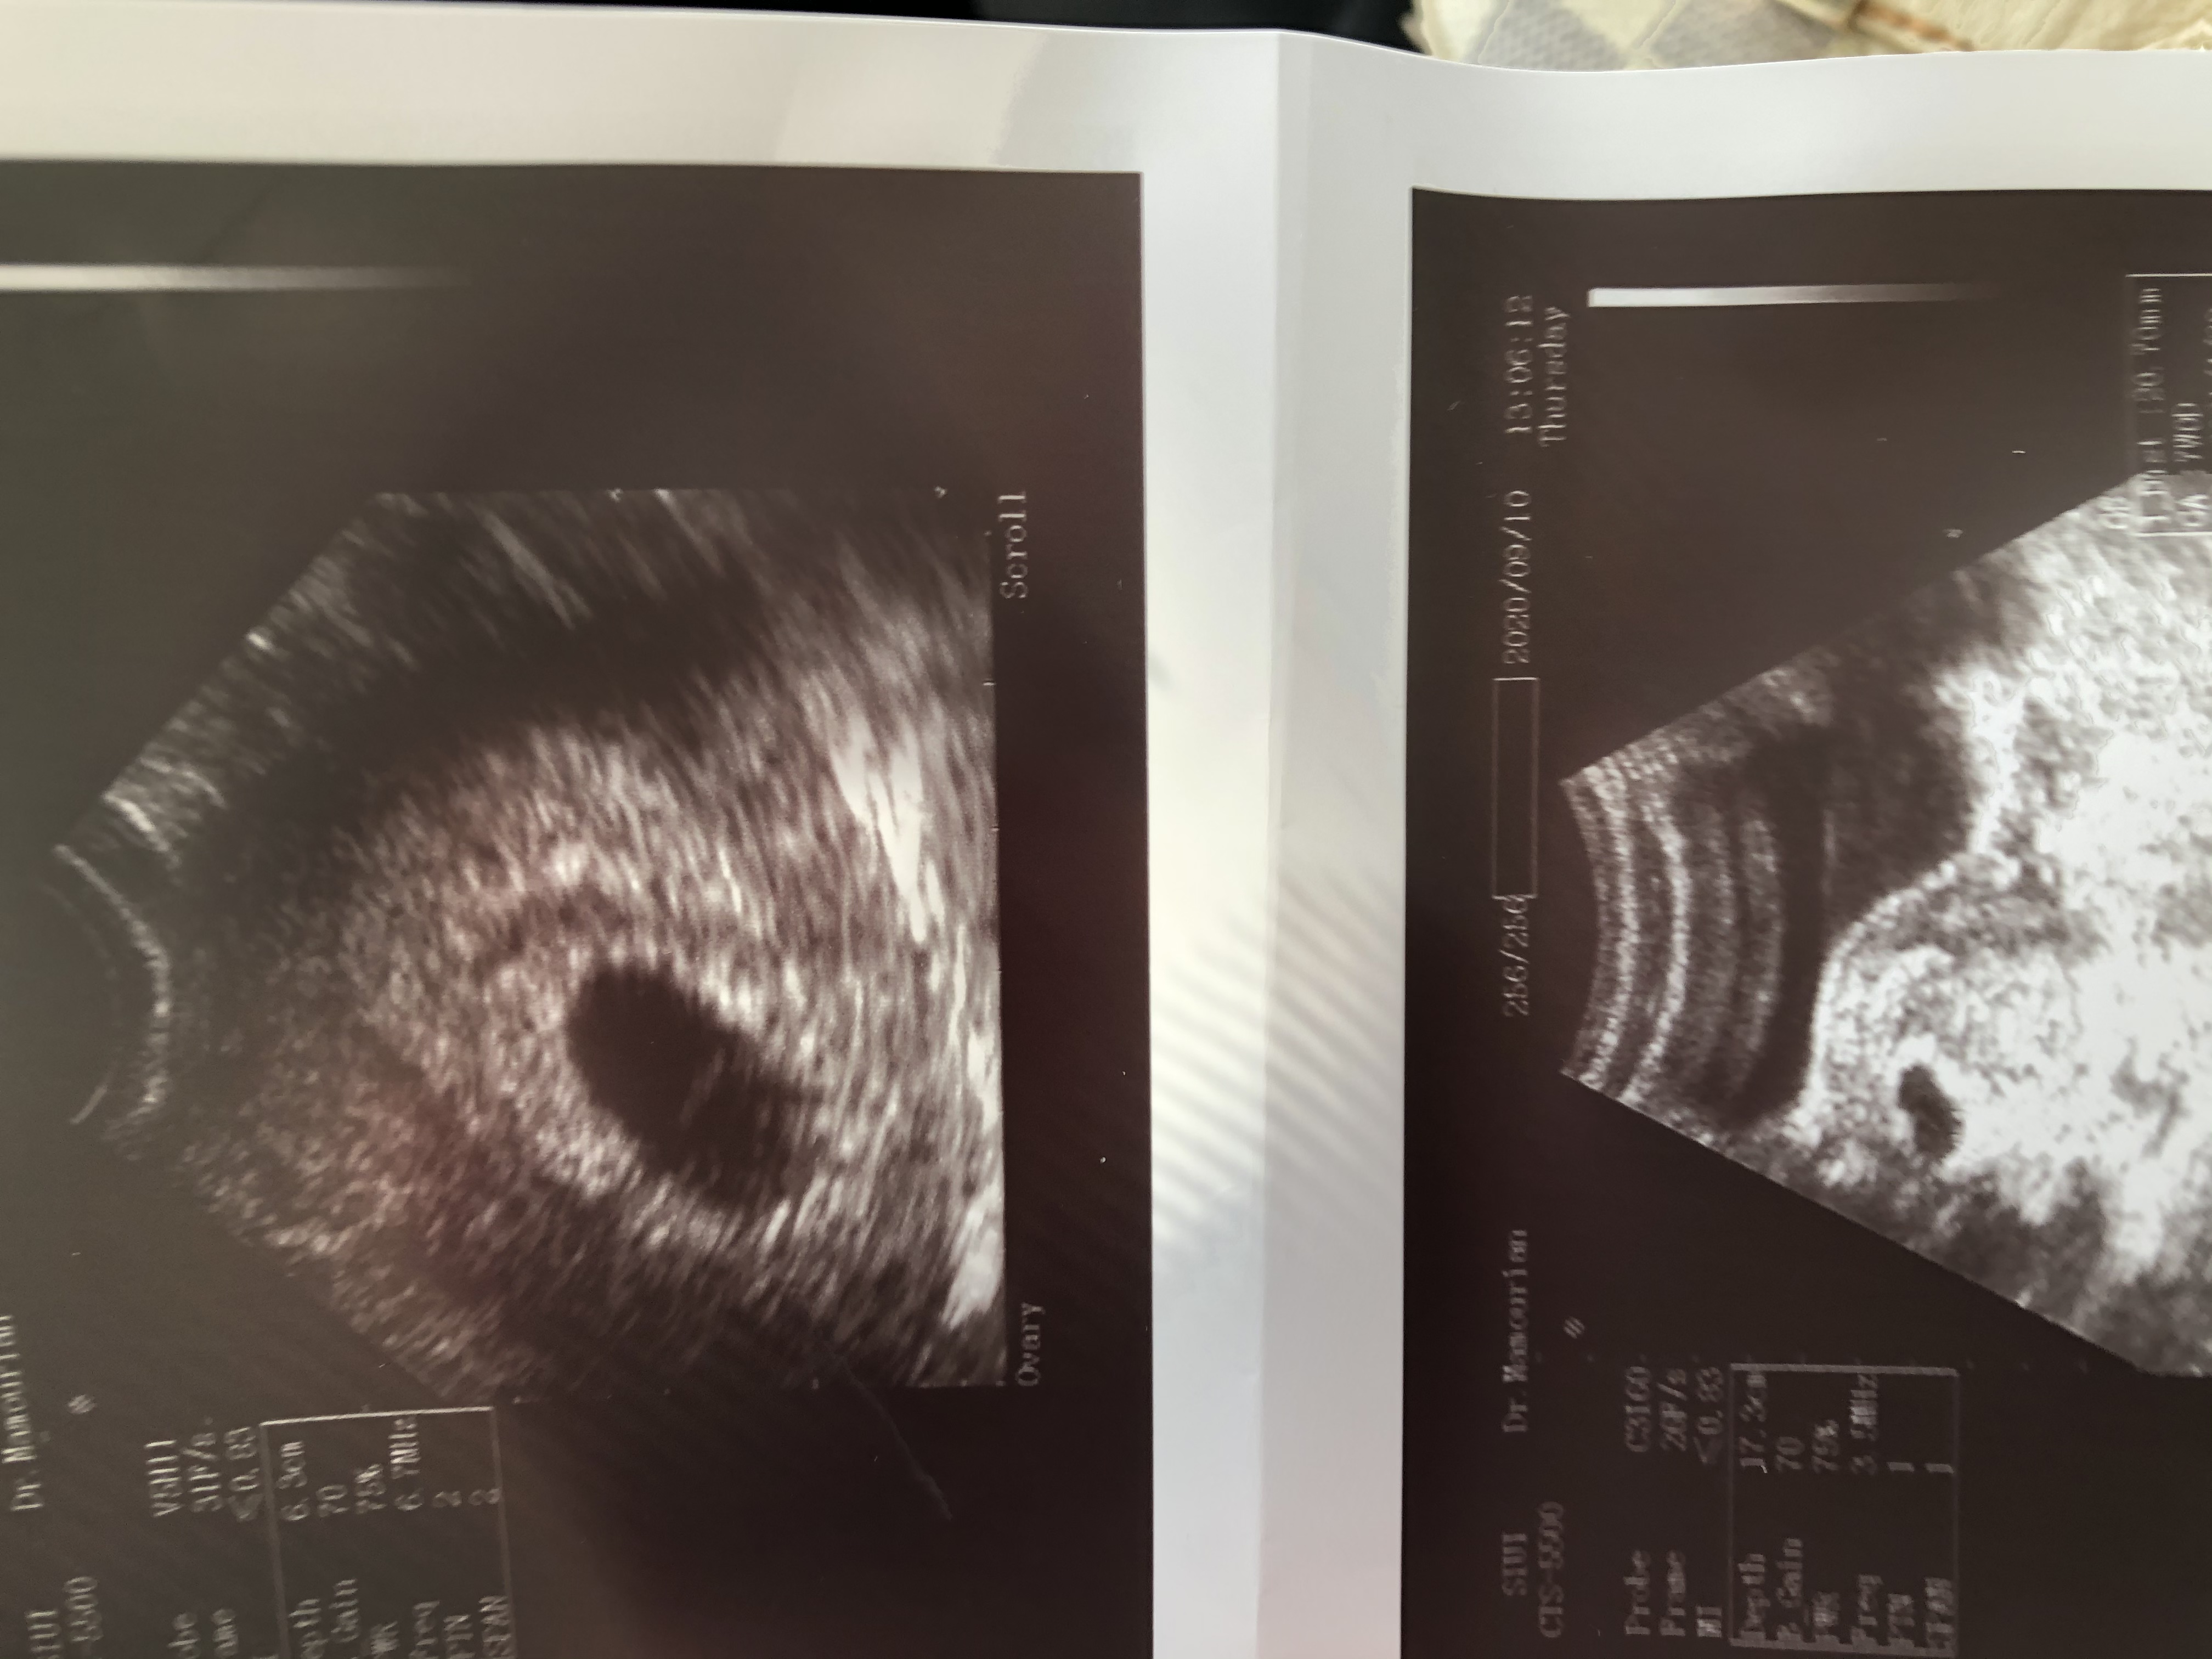

دوستان من از اولين تاريخ پريودم ٨ هفته ميگذره ولي سونو گفت ٧هفته

حالا اينكه توي هفته ٧ با سونوي واژينال قلب مشخص نشه طبيعيه؟؟؟

قلب رو معمولا تا ۸هفته صبر میکنن

و تازه شنیدم یکسری دکترهای قدیمی تا ۱۰ هفته هم صبر میکنن

منم بهت توصیه میکنم صبر کنی

ببین تاریخ اخرین پری دو هفته تفاوت داره

مگه نمیگن ۱۴روز بعد پری تخمکگذاری اتفاق میافته

خب احتمال بارداری دو هفته بعد از تاریخ آخرین پریوده

پس همیشه ۲ هفته تفاوت وجود داره با چیزی که دکتر میگه با واقعیت جنین

عزیزم من دقیقا شیرایط شما رو داشتم الان ۳هفته هست کورتاژ کردم ولی تا۱۰هفته تمام صبر کردم ومنتظر موندم هر هفته هم سونو بودم بنظرم بزار آخر۸هفته برو ی جای خوب سونو معتبر ومعروف باشه ک خیالتم راحت بشه انشاالله ک تشکیل میشه ولی نگران نشو برای بعضیا دیر تشکیل میشه